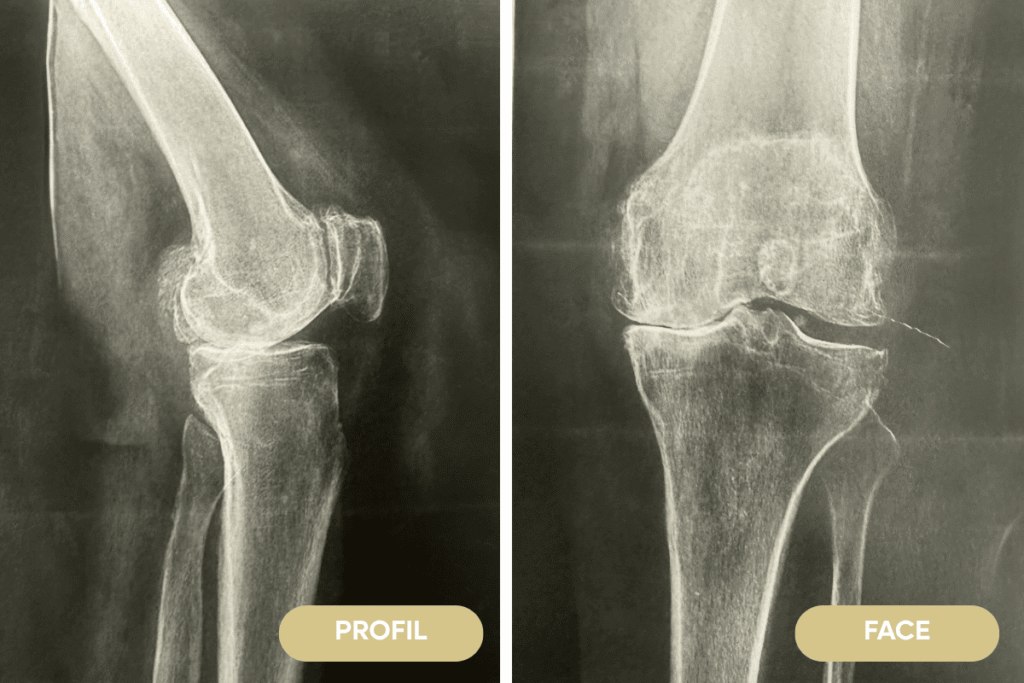

Arthrose de genou

Qu’est ce que l'arthrose de genou ?

Lorsque le cartilage s’use on parle d’arthrose, les surfaces articulaires ne sont plus lisses, le glissement n’est plus libre, il se produit des douleurs, des accrochages. Lorsque le cartilage disparaît : l’os est à nu devient de plus en plus douloureux et se défend en fabricants des excroissances osseuses qui rendent l’articulation de plus en plus raide.

Les causes de l’arthrose de genou sont très nombreuses par exemple : vieillissement, surpoids, déformation du membre inférieur, hérédité, maladies métaboliques, causes génétiques et surutilisation

Les douleurs augmentent notamment lors de la marche ou des changements de positions, ces douleurs siègent habituellement autour du genou. L’articulation devient de plus en plus raide, il devient difficile de fléchir (plier) le genou, parfois l’étendre complètement devient impossible, le genou peut se déformer et ne plus être stable.